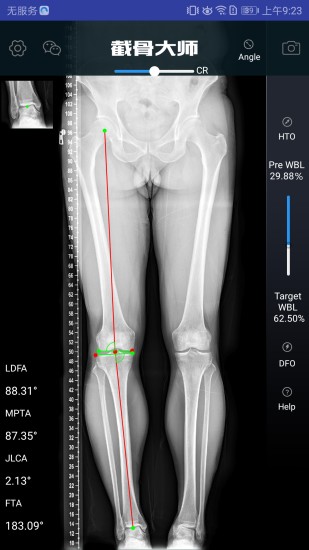

自动计算截骨矫正角度、楔块高度、切锯深度与脚长变化。

设定期望WBL,矫正角度,缺口高度,MPTA或LDFA

计算术前负重线(WBL)和规划目标WBL。

提供開放(open)或閉合(close)、内侧(medial)或外侧(lateral)截骨。

模拟截骨调整后结果。